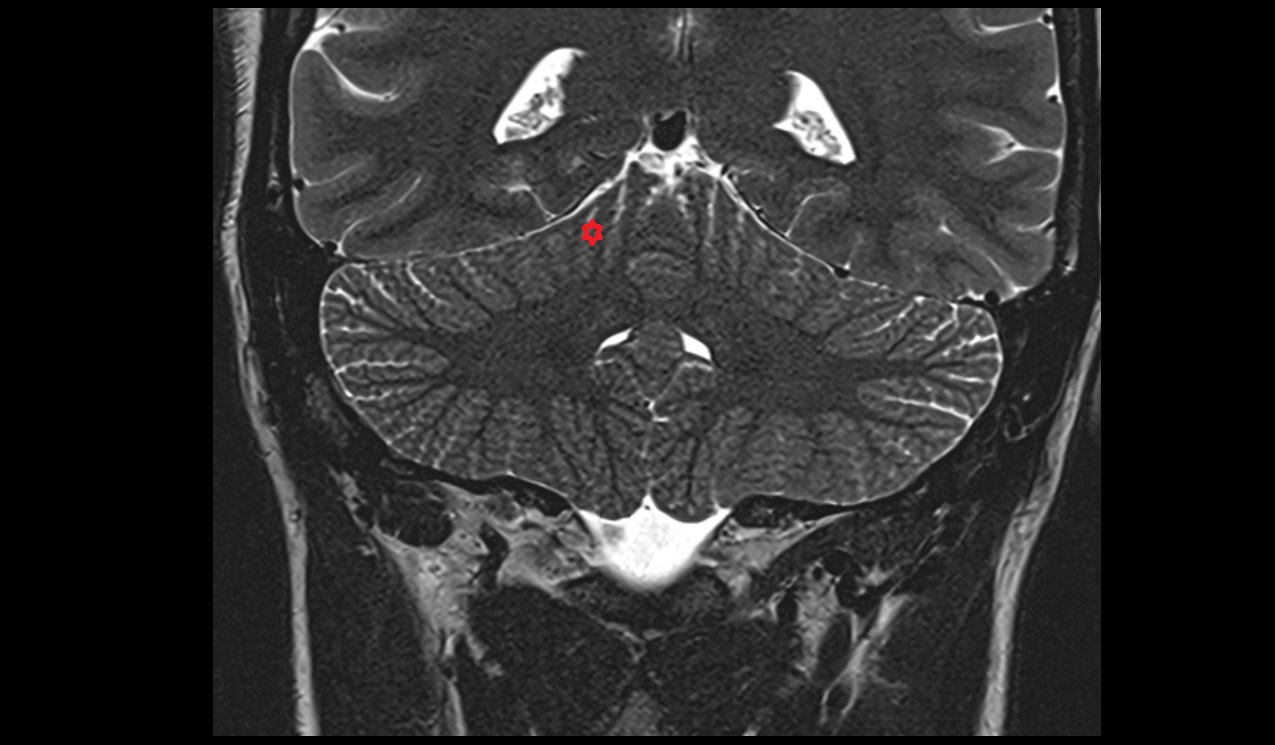

- Cerebellum